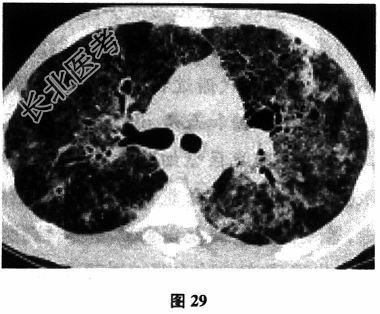

- [材料题] 患者女性,43岁,反复咳嗽、咳痰半年,加重伴气短2个月。胸部CT(图29):示双肺弥漫间质病变呈网状,合并磨玻璃样改变。曾因贫血有异体输血史。查体:呼吸浅快,双肺未闻及干湿啰音,心腹未见明显异常。实验室检查:人类免疫缺陷病毒(HIV)抗体检测2次均阳性。CD4淋巴细胞160个/μl。